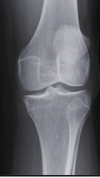

AP knee criteria (5)

open joint space (lat) tibial spines centred to tunnel lat tib plateau in a single line patella slightly lat to midline lat condyle of tibia superimposes half the fibular head

on an AP knee, if the fibular head is too high, what does that indicate

too much caudad angle

on an AP knee, if the fibular head is too low, what does that indicate

not enough caudad angle

correction

more caudad angle

less external rotation